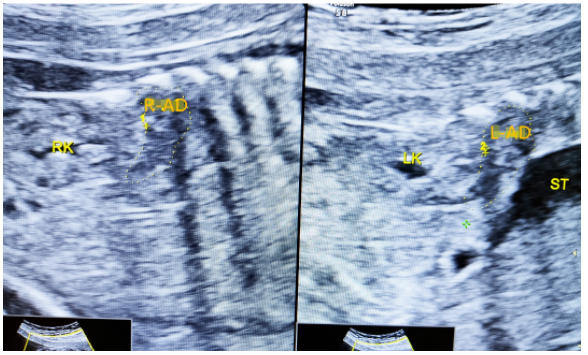

一、肾缺如表现为肾区无肾脏回声,肾上腺平卧。

上图示双肾缺如,肾上腺平卧。

上图示正常双肾及肾上腺。(R-adrenal gland/R-AD:右侧肾上腺,L-adrenal gland/L-AD:左侧肾上腺,RK:右肾,LK:左肾,liver:肝,st:胃)